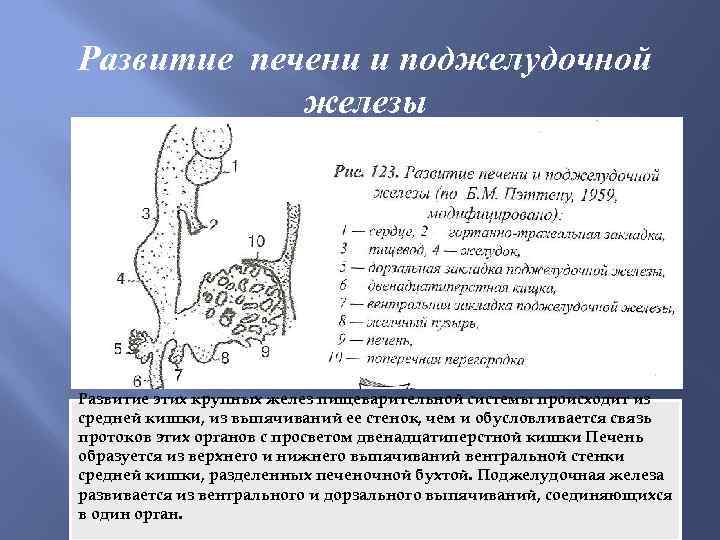

Развитие печени и поджелудочной железы Развитие этих крупных желез пищеварительной системы происходит из средней кишки, из выпячиваний ее стенок, чем и обусловливается связь протоков этих органов с просветом двенадцатиперстной кишки Печень образуется из верхнего и нижнего выпячиваний вентральной стенки средней кишки, разделенных печеночной бухтой. Поджелудочная железа развивается из вентрального и дорзального выпячиваний, соединяющихся в один орган.

Развитие печени и поджелудочной железы Развитие этих крупных желез пищеварительной системы происходит из средней кишки, из выпячиваний ее стенок, чем и обусловливается связь протоков этих органов с просветом двенадцатиперстной кишки Печень образуется из верхнего и нижнего выпячиваний вентральной стенки средней кишки, разделенных печеночной бухтой. Поджелудочная железа развивается из вентрального и дорзального выпячиваний, соединяющихся в один орган.